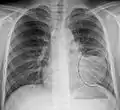

Normal AP CXR

Normal lateral CXR